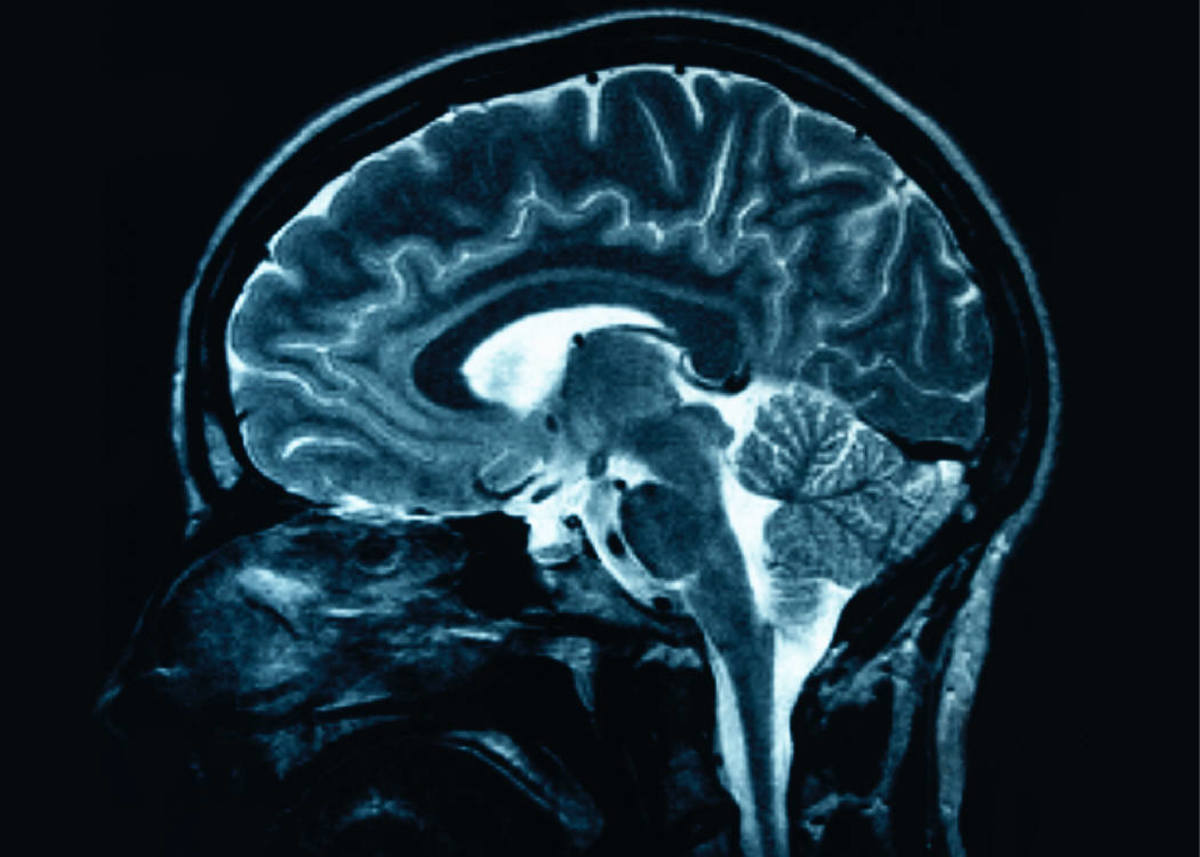

Brain Injury Scan

Altered consciousness is certainly the first symptom to recognize. Seizures and fluid that is built up in the brain are serious symptoms. If there is a penetrating head wound then infection is a possibility. A bleed in the brain is very significant and it may be diagnosed by an MRI. The MRI can also show a small area of bruising (contusion) or scarring (gliosis). Complaints of vertigo and headaches are also important.